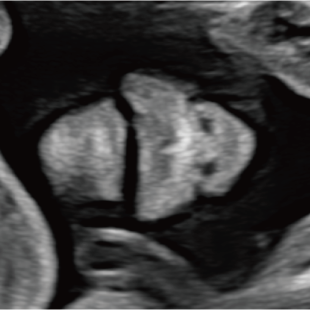

赤ちゃんの3~5%は、何らかの病気や医学的な介入を要する状態をもって生まれてくるといわれており、その中には、妊娠中・出生時・出生後に緊急の対応を要するものも含まれます。 特に先天性心疾患は比較的頻度が高く、約100人に1人の赤ちゃんが先天性心疾患を合併し、重症度や緊急性の高い症例(生後に入院や手術が必要な症例)は約1000人に4人といわれています。

胎児超音波スクリーニングは、このような異常をできるだけ早期に見つけ、赤ちゃんの状態にあわせて安心・安全なご出産を迎えていただくための検査です。もし何らかの異常が見つかった場合にはご出産前に超音波専門医・指導医による精査、必要に応じて臨床遺伝専門医***による遺伝カウンセリング、小児科医・小児外科医による詳細な診察や出生後についてのカウンセリングを受けて頂くことが出来ます。